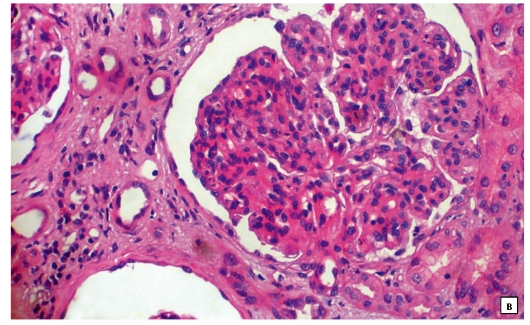

Механизм остро го диффузного гломерулонефрита